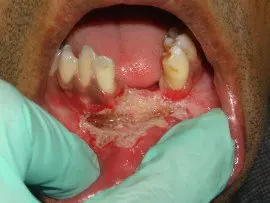

Periodontal Plastic Surgery consists of major procedures like Frenectomy & Vestibuloplasty, Soft Tissue Grafting, Barrier Membrane Techniques etc.

Frenectomy a minor procedure done to remove high frenum, which causes pulling of gum tissue [gingival recession]. High frenum also causes  spacing in between teeth creating cosmetic & functional problems.

Vestibuloplasty is also a similar procedure but intended to remove high attached tissue  to get a good depth.

Recently with use of soft & hard tissue lasers both these procedure have become very easy, bloodless & comfortable to the patient,